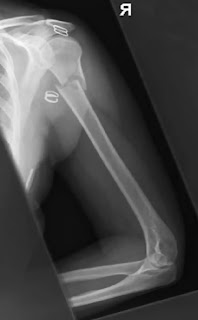

fractured humerus x-ray

1. Humerus Antero-posterior – erect

2. Humerus lateral erect